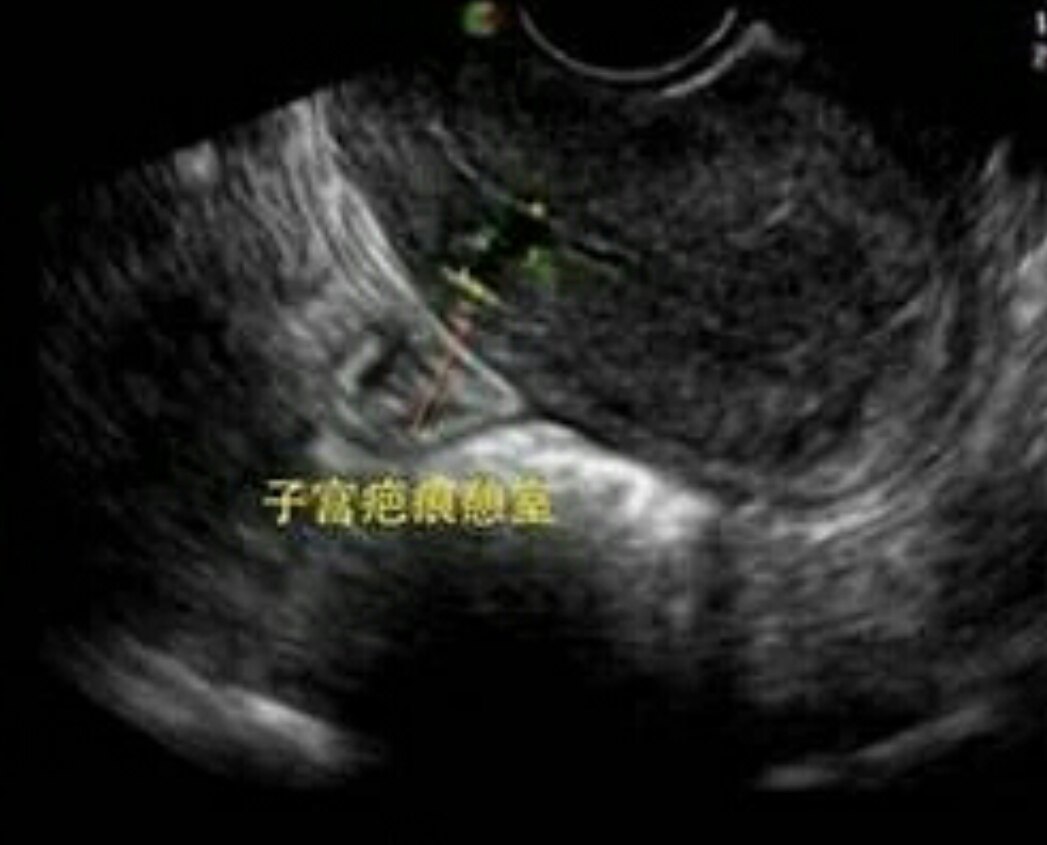

子宫疤痕憩室的图片

剖宫产瘢痕憩室,被定义为子宫下段肌层内的低回声区,这反映了既往剖宫

瘢痕憩室也就是子宫憩室,特指剖宫产术后子宫切口愈合不良,子宫瘢痕处